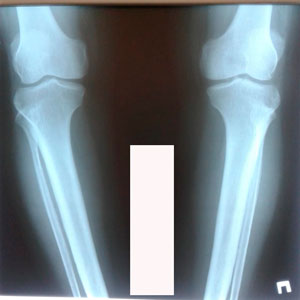

Исходник - 45 лет.

Дата операции - 09.06.2020

до круток